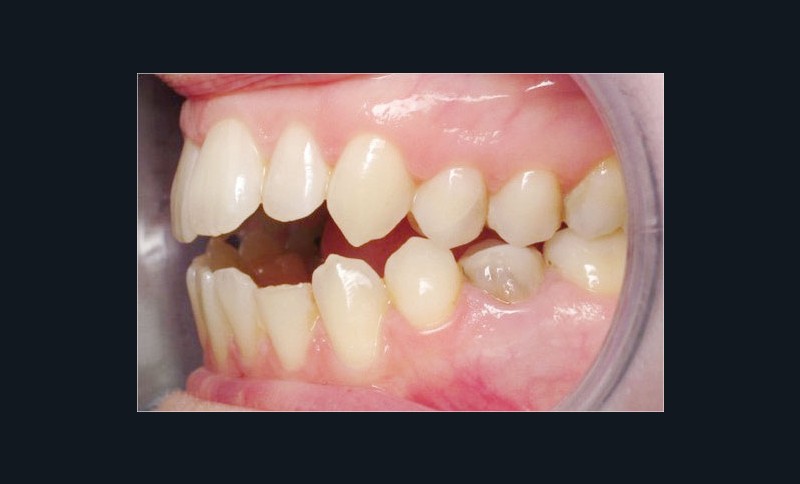

Les empreintes ont été réalisées en sillcone wash technique et adressées au laboratoire Insignia. Actuellement, nous réalisons ces empreintes à l’aide de la caméra intra-orale Lythos et la fiche patient est initialement créée sur la caméra. Le transfert des empreintes au laboratoire est immédiat et le risque d’erreurs considérablement réduit (fig. 4 à 6).